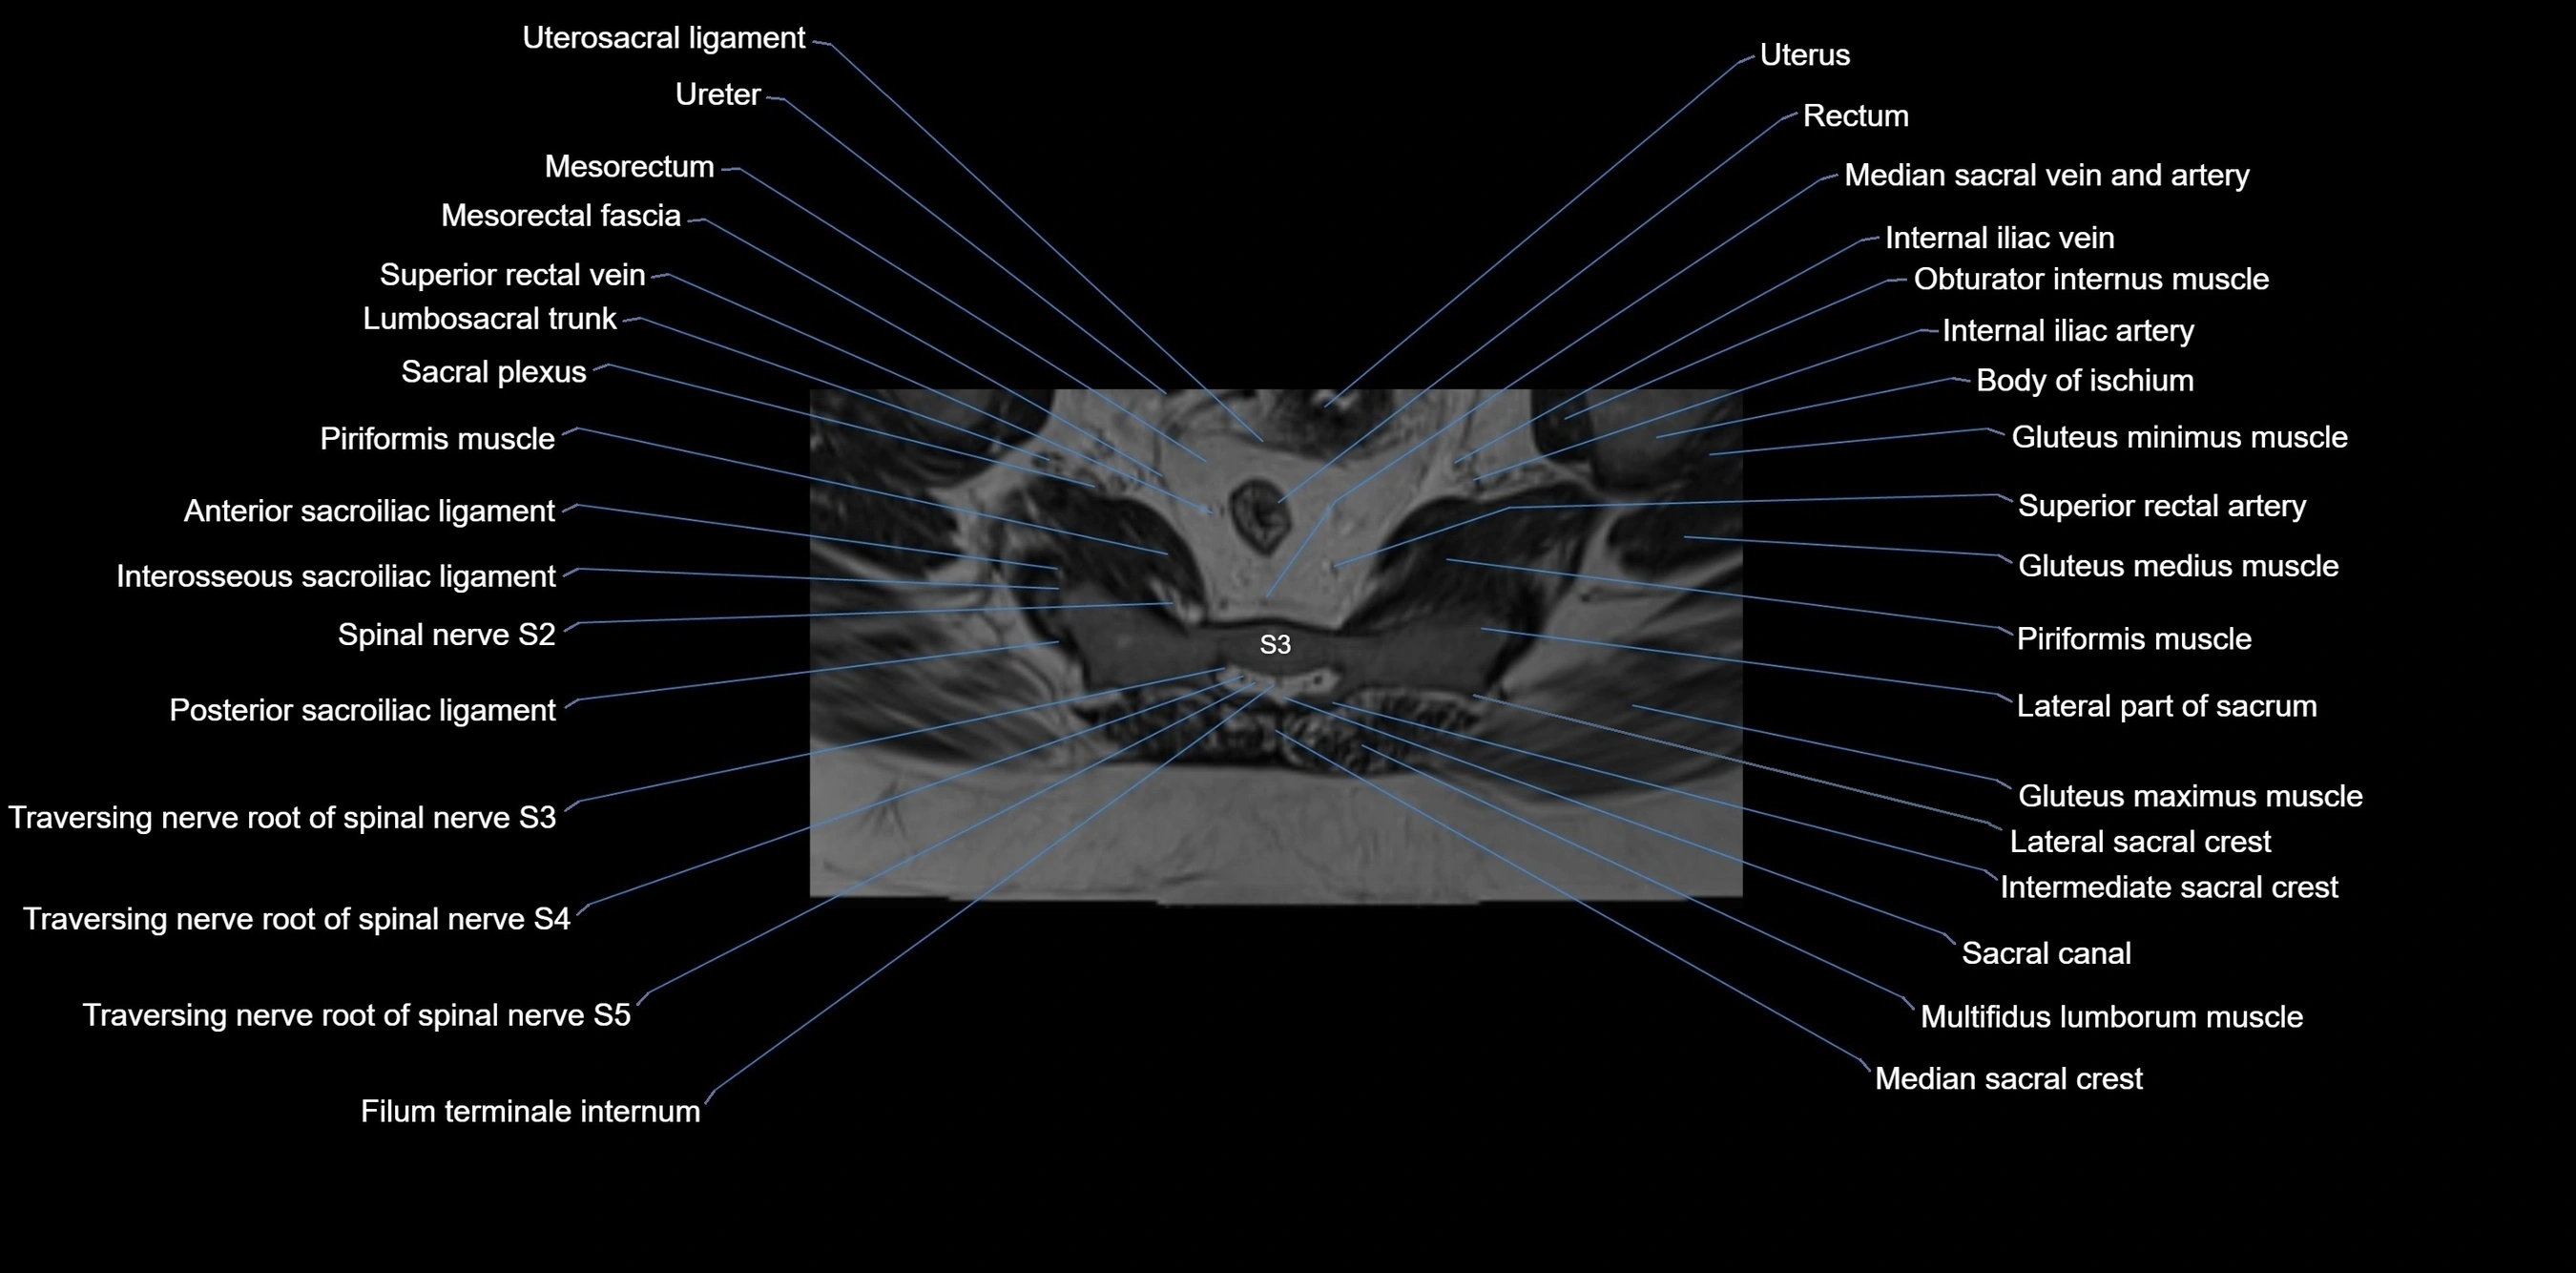

CT image

image